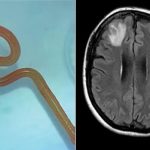

برازیلین خاتون کھانا پکاتے ہوئے مرچوں کی خوشبو سُونگھنے سے جان کی بازی ہار گئیں۔ غیر ملکی میڈیا رپورٹس کے مطابق 25 سالہ تھائیس میڈیروس اپنے خاندان کے لیے کھانا پکانے میں مصروف تھیں کہ انہوں نے غیر ارادی طور پر کھانے میں شامل کی گئی کالی مرچ کی خوشبو سونگھ لی جس کے سبب مزید پڑھیں